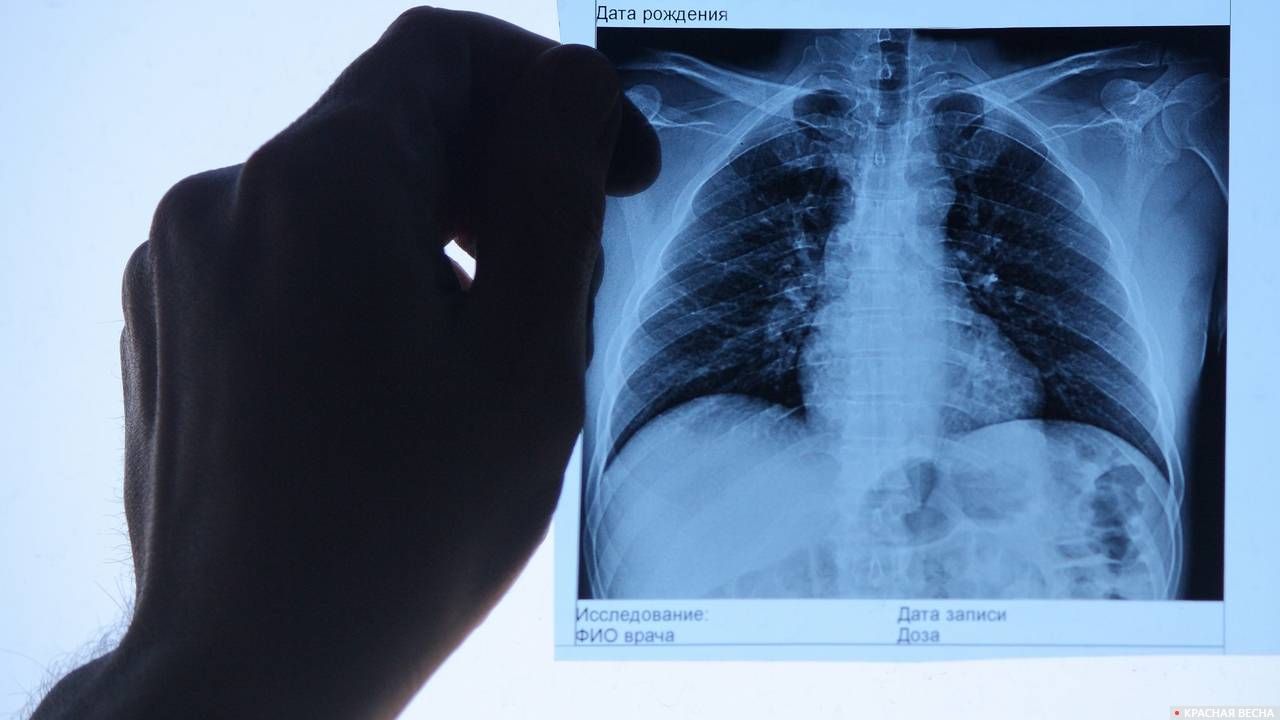

Поражение легких является одним из основных симптомов коронавируса (COVID-19). В данной статье представлены фото рентгеновских снимков, которые позволяют визуально оценить состояние легких при этом заболевании.

На фотографиях рентгеновских снимков видно, как вирус воздействует на легочную ткань. Характерные признаки поражения легких включают пятна, инфильтраты и наличие жидкости внутри легочных альвеол.

Фото рентгеновских снимков помогают врачам и специалистам визуально определить степень поражения легких и принять соответствующие меры лечения и поддержки пациента.